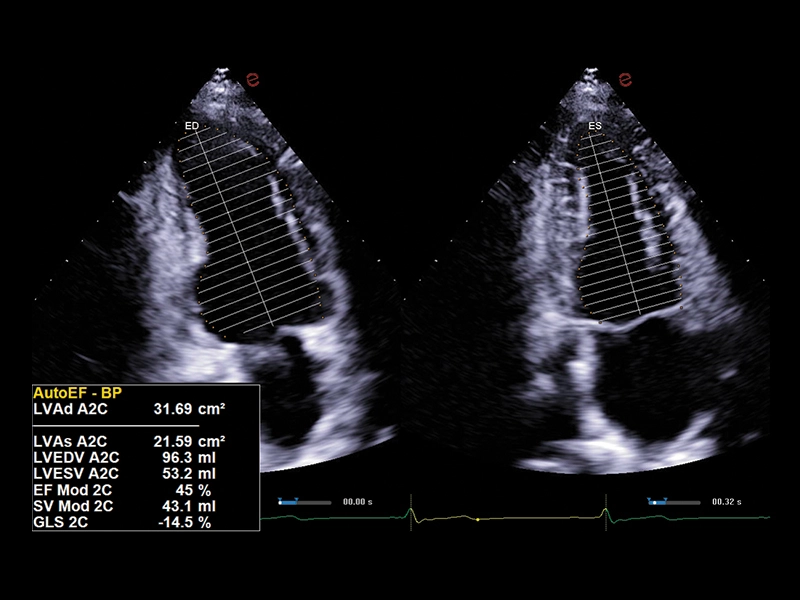

MyLab™E80 - AutoEF

MyLab™E80 - AutoEF

MyLab™Omega eXP - AutoEF

MyLab™Omega eXP - AutoEF

MyLab™X90 - AutoEF Automatic Ejection fraction assessment of the left ventricle

MyLab™X90 - AutoEF Automatic Ejection fraction assessment of the left ventricle

MyLab™X5 - AutoEF

MyLab™X5 - AutoEF

MyLab™X6 - AutoEF

MyLab™X6 - AutoEF

MyLab™X7 - AutoEF

MyLab™X7 - AutoEF

MyLab™Omega - Zero-Click AutoEF

MyLab™Omega - Zero-Click AutoEF

MyLab™A50 - AutoEF

MyLab™A50 - AutoEF

MyLab™A70 - AutoEF

MyLab™A70 - AutoEF